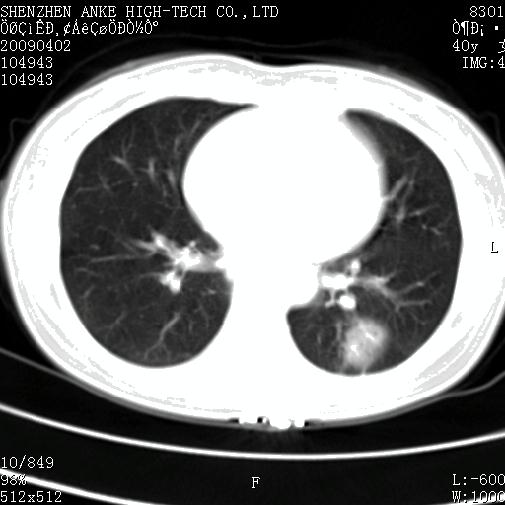

以下是引用随光逐影在2009-4-2 12:16:00的发言:[br]考虑左肺下叶背段继发性肺结核,结核球形成;建议追踪复查。

以下是引用gudu医生在2009-4-2 11:27:00的发言:[br]周围型肺癌

以下是引用卜一在2009-4-2 13:31:00的发言:[br][br] [br] 空洞壁厚不均 胸膜凹陷征。周围型肺癌可能 不排除干酪坏死型肺结核及坏死性肉芽肿。 [br] [br]支持!

以下是引用ct诊断高手在2009-4-2 13:04:00的发言:[br]空洞壁厚不均 胸膜凹陷征。周围型肺癌可能 不排除干酪坏死型肺结核及坏死性肉芽肿。